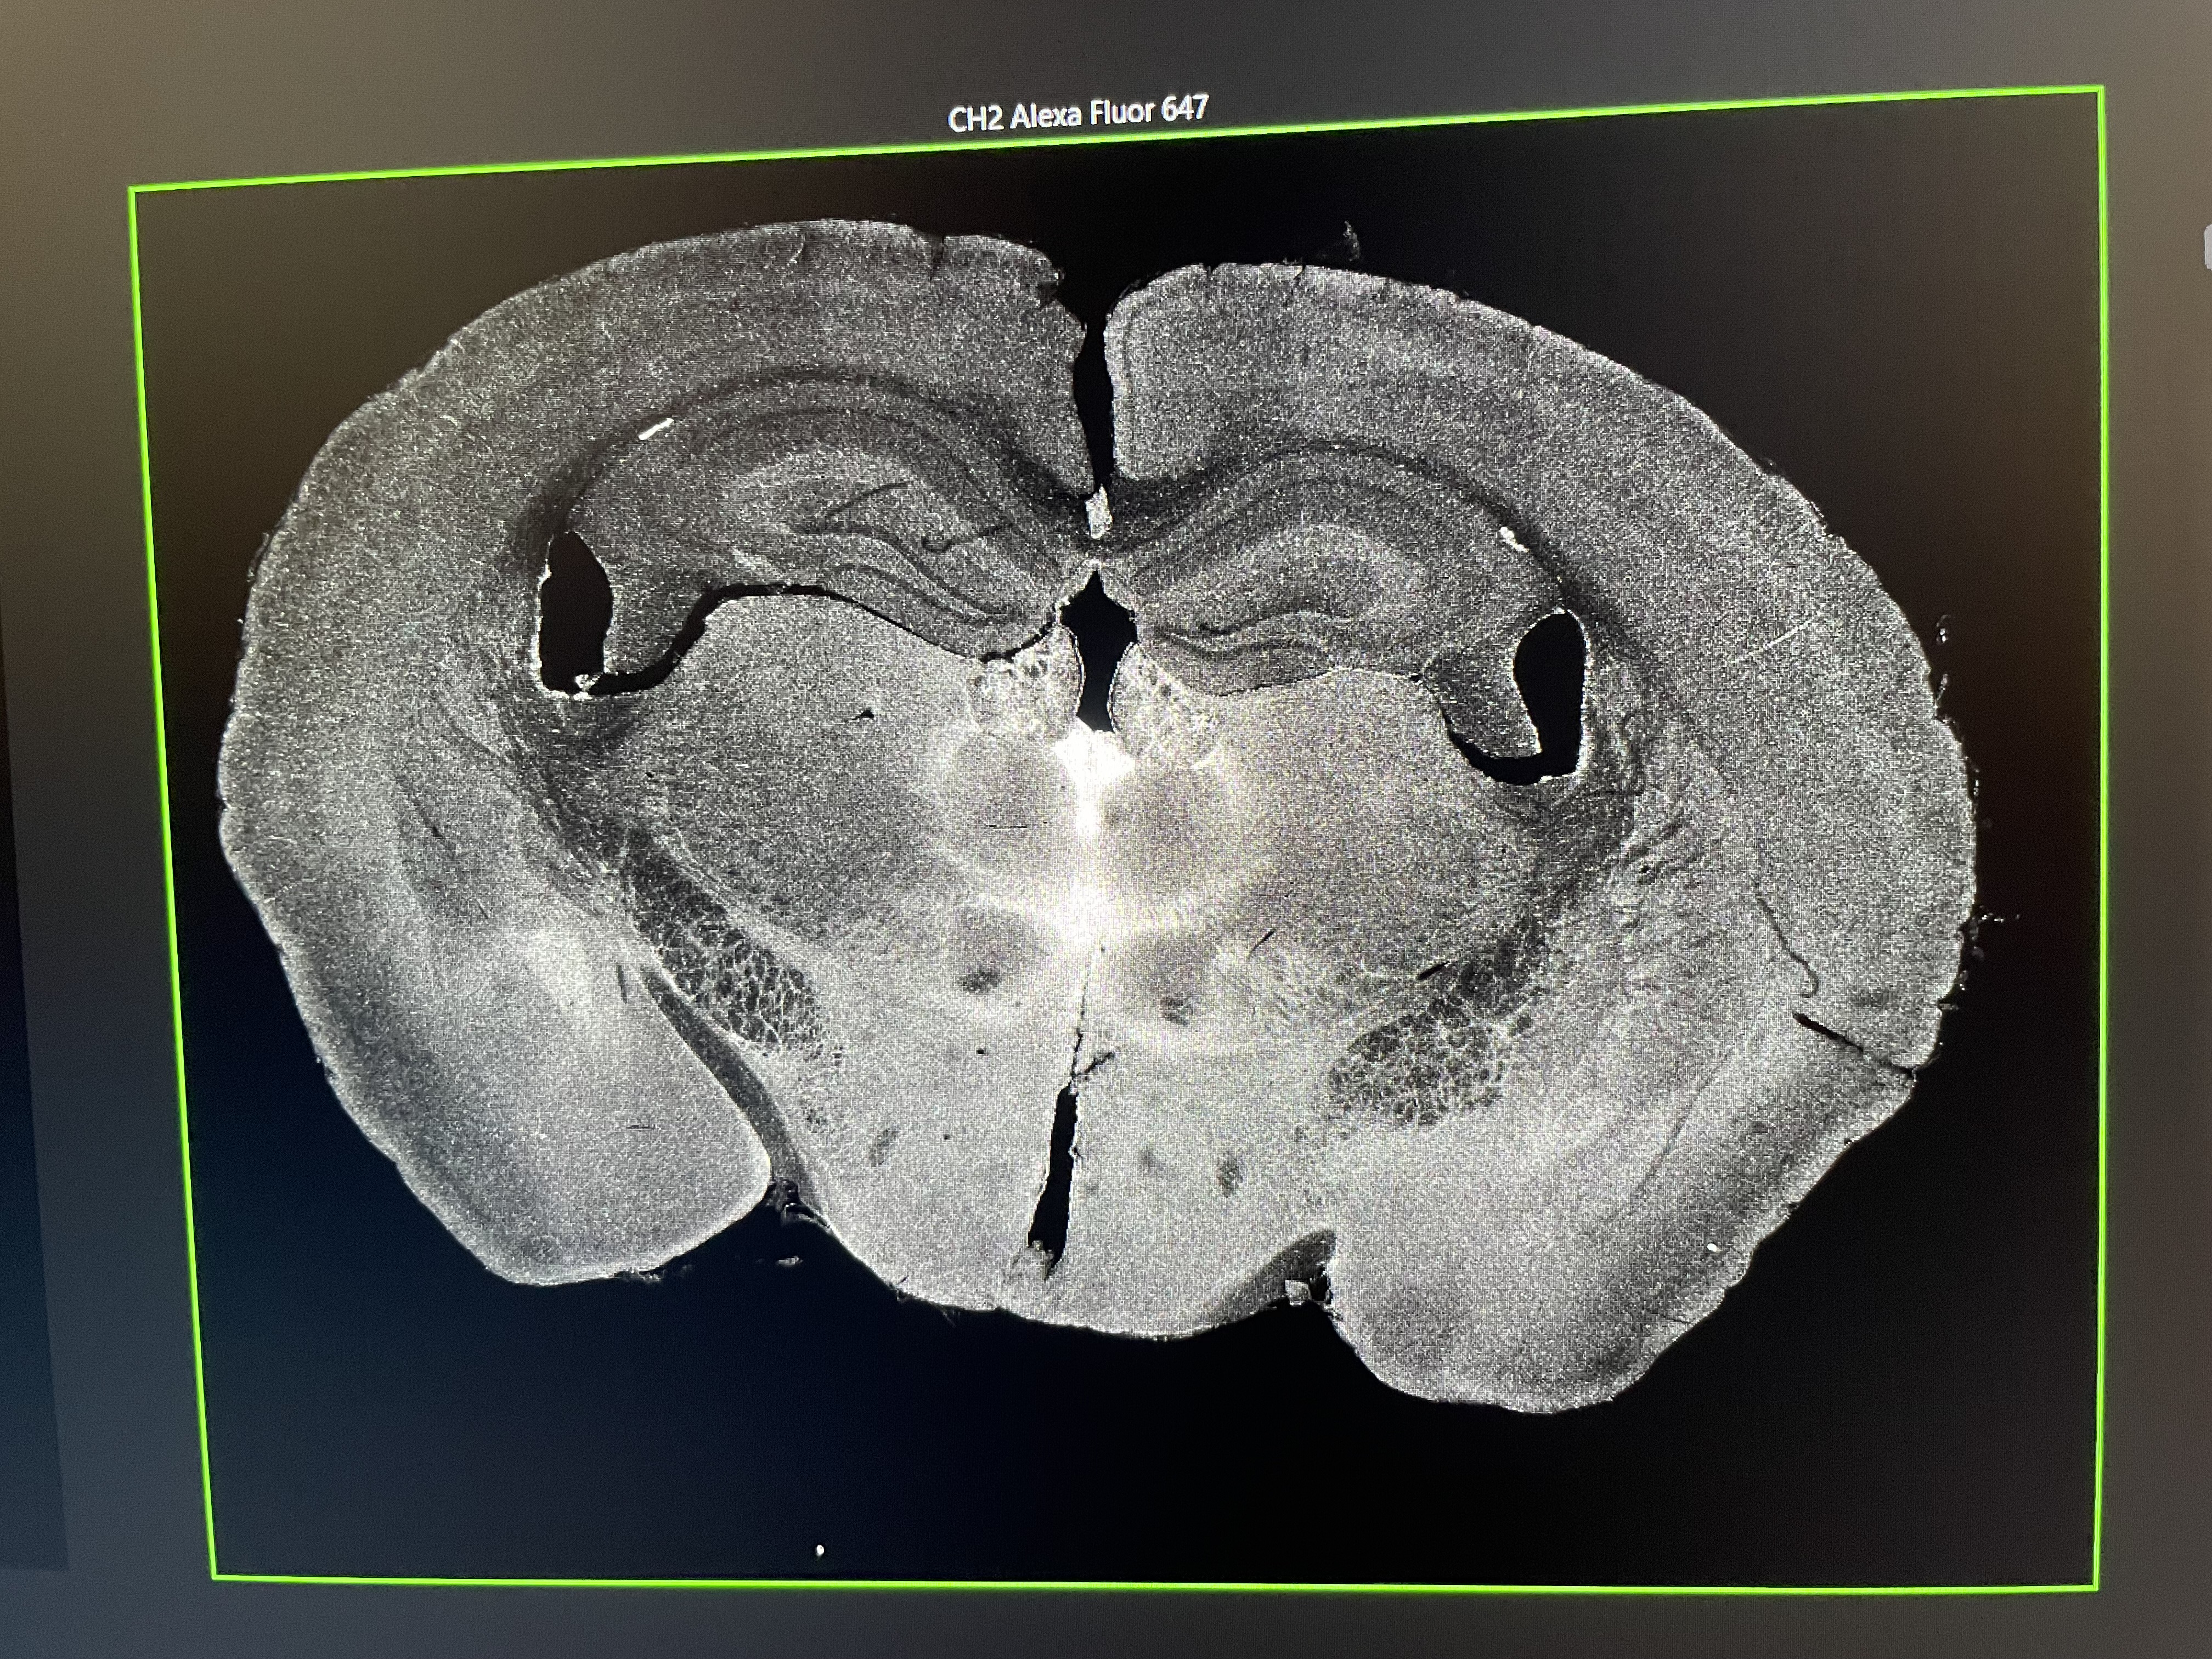

I can’t believe Friday is my last day at the Ye Lab. I have had such an amazing experience and met so many wonderful people and I am so grateful to everyone who made it possible, especially Sarah Holbrooke, my amazing mentor Cailynn Wang, Ben Pang, Jennie Thomas, and all my fellow San Diego interns! Friday morning began by mixing 8mL of the CLICK reaction buffer (which includes DMSO, PBS, an azide, CuSO4, and BTTP). I then pipetted 975 uL into each of my 6 wells containing the best tissue sample for each organ and condition (vehicle or drug for the brain, liver, and kidney) and added 25 uL of sodium ascorbate to initiate the CLICK reaction. After letting the reaction run on the shaker for 1 hour I removed the tissue and washed it with PBST-EDTA 3 times. I finally stained the tissue with the DAPI stain before mounting it on a slide for imaging. Before we turned on the confocal microscope, Cailynn warned me not to be disappointed if no drug signal showed up because it was my first experiment and experiments often don’t go as expected on the first try. To her surprise, however, when we turned the laser to the proper light wavelength (647 nm), there was a strong drug signal from the pargyline in the experimental brain and none in the vehicle/control brain (which was a great result and meant my experiment had been done correctly!). I was so pleased that it had worked because I had struggled a bit with the pargyline injection and we weren’t certain the drug had been properly delivered to the brain. After imaging, Ben treated me to some boba to celebrate my time in the lab and we exchanged parting cards. I said goodbye to everyone in lab and walked out for the final time, so grateful for my experiences there but excited to return to the mountains.

The image of my drug (pargyline) injected brain on the confocal microscope. The white enrichment represents the successful drug signal where it binds in the brain. I discovered that pargyline most prominently binds in the paraventricular nucleus of the thalamus (the brightest white area in the center).